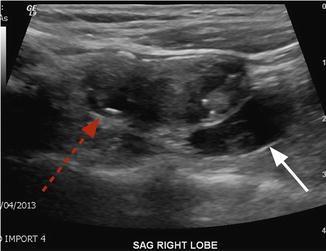

- Ultrasonido de cuello y tiroides:

- No se debe utilizar para confirmar el diagnostico de HPTP

- La única razon por que el Dr. Rodrigo Arrangoiz lo solicita es para descartar patología en la glándula tiroides:

- Nódulos tiroides sospechosos para malignidad